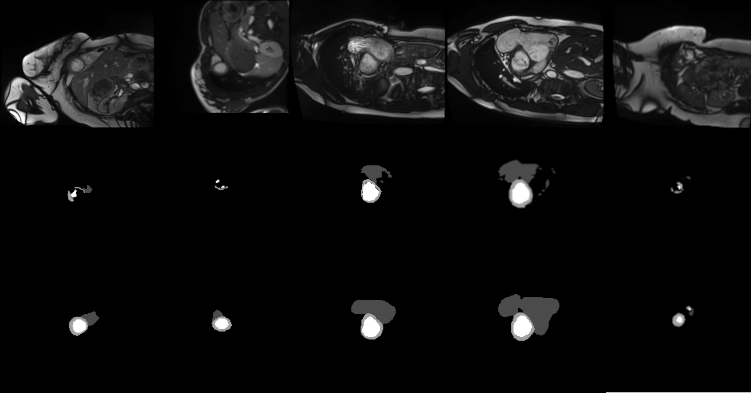

To test the effectiveness of our proposed gated shape stream, we conducted ablation studies on our model using the AC17 dataset. Results reported in Table 3 are from our validation set of our proposed model with and without the shape stream. Both models were trained with learning rate 5E-4 and RAdam. The results reported are the models taken at the convergence epoch. Both models were then evaluated on the test set. Figure 2 shows some cases from the test set where the model with the shape stream visibly outperforms its counterpart.

Refer to caption

Figure 2: Top: original MRI image. Middle: model without shape stream prediction. Bottom: model with shape stream prediction. Higher quality segmentations with the correct shapes of the classes are made using the shape stream.